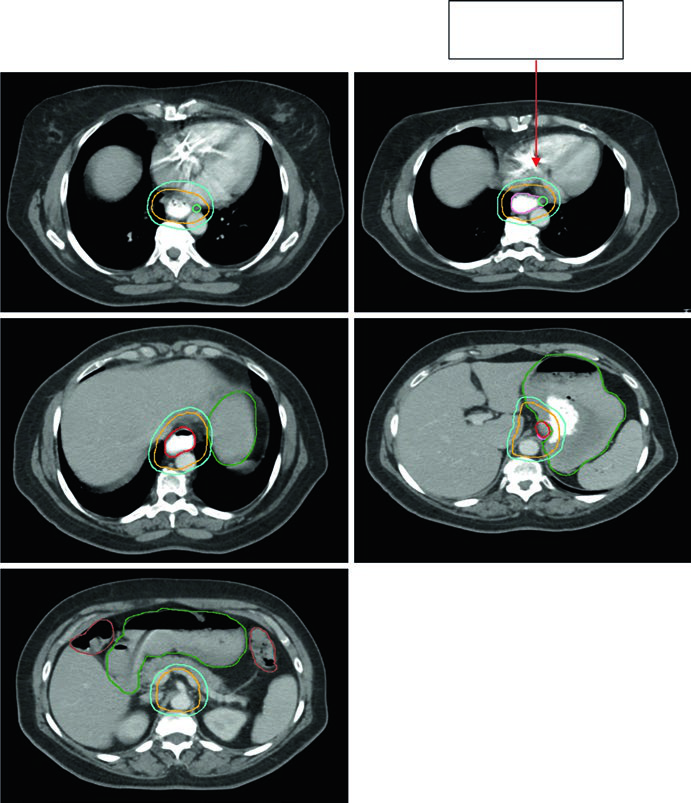

Caso 2: Adenocarcinoma Torácico Inferior — 81 anos, uT3N1

Paciente de 81 anos com adenocarcinoma esofágico torácico inferior uT3N1. O PET demonstrou captação no primário e no linfonodo paratraqueal nível 4R. A endoscopia revelou adenocarcinoma circunferencial parcialmente obstrutivo entre 31 e 35 cm dos incisivos. O EUS confirmou doença T3 com linfonodo nível 4R suspeito. Os contornos aplicaram margem de 0,5 cm de GTV para CTV no linfonodo 4R e cobertura inferior de 3–4 cm. Volumes: plexo braquial (roxo), estômago (verde escuro), GTV esofágico (vermelho), ITV (rosa), GTV nodal (verde claro), CTV (laranja), PTV 50,4 Gy (azul escuro).